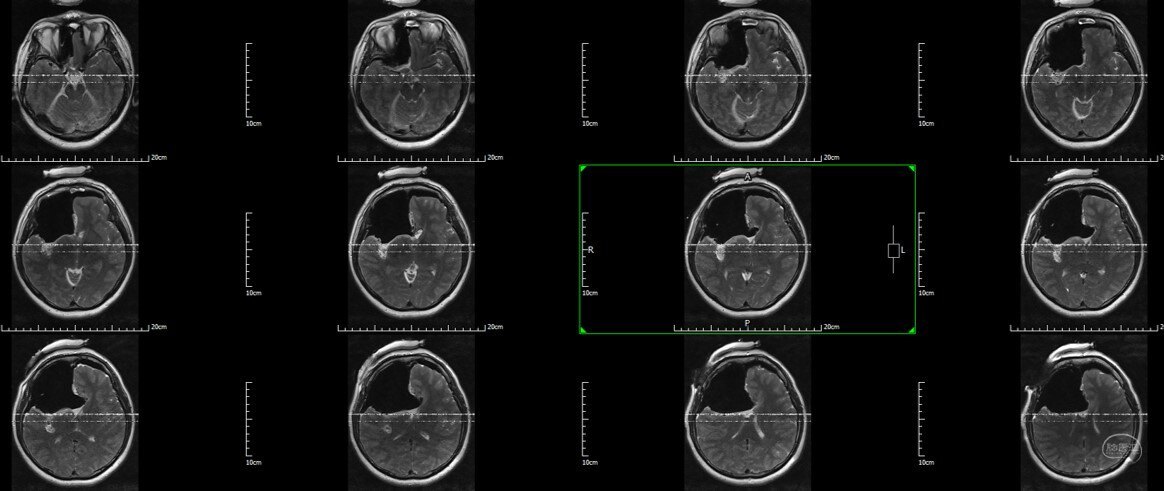

不幸的是,2年后迅速复发,再次手术(此次)。肿瘤出现强化,肿瘤通过胼胝体向左额进展,右侧岛叶也信号异常,膨胀性改变。术前诊断:右额-胼胝体-岛叶胶质瘤

术前增强T1

术前T2 Flair:右额-胼胝体-岛叶胶质瘤

术前T2